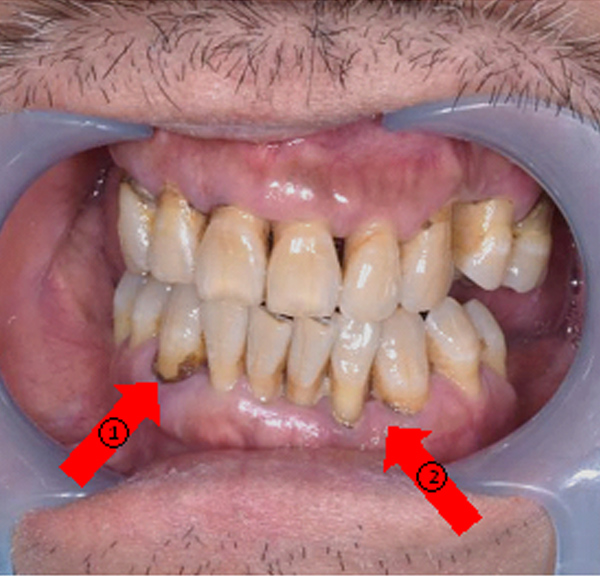

噴砂治療為牙周病及人工植體周圍炎治療前預備治療,於煙癮或者嚼食檳榔患者身上,在開始主療程前先以噴砂方式清除菸垢及檳榔垢後,露出乾淨牙根表面,再開始進行牙周病治療,提升治療成效。

紅色箭頭:(噴砂前)菸垢及檳榔垢嚴重堆積。

黃色箭頭:(噴砂後)牙齒牙根表面乾淨,醫師得以仔細檢查牙周病以及植體感染源。